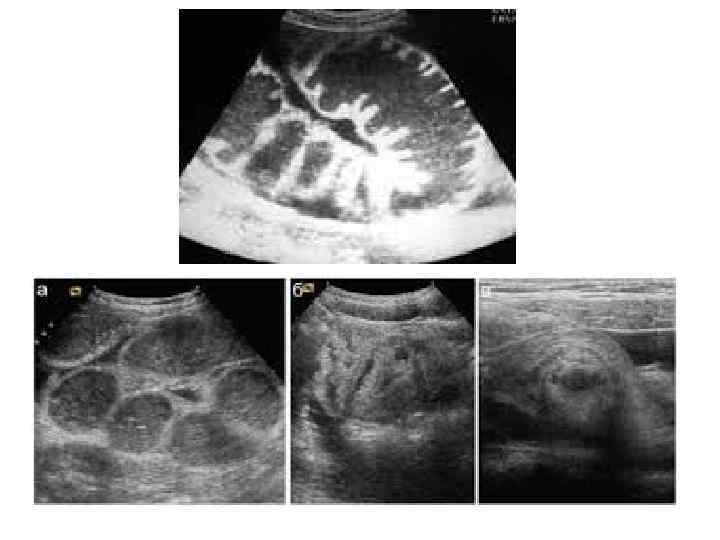

• Рентгенография брюшной полости: определение газа и уровней жидкости в петлях кишок (чаши Клойбера) поперечная исчерченность кишки (симптом керкринговых складок) • УЗИ: • при механической кишечной непроходимости: расширение просвета кишки более 2 см с наличием феномена «секвестрации жидкости» в просвет кишки; утолщение стенки тонкой кишки более 4 мм; наличие возвратно поступательных движений химуса по кишке; увеличение высоты керкринговых складок более 5 мм; увеличение расстояния между керкринговыми складками более 5 мм; гиперпневматизация кишечника в приводящем отделе • при динамической кишечной непроходимости: отсутствие возвратно поступательных движений химуса по кишке; феномен секвестрации жидкости в просвет кишки; невыраженный рельеф керкринговых складок; гиперпневматизация кишечника во всех отделах